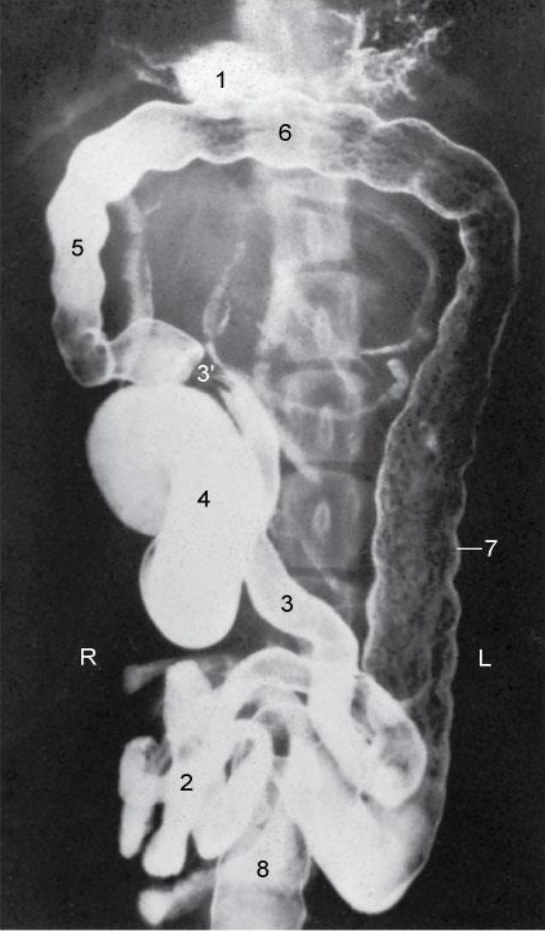

Re. 3 regions of colon. topography?

ascending colon - right side

transverse - colon cranial to the root of mesentery (right side)

descending colon - left side